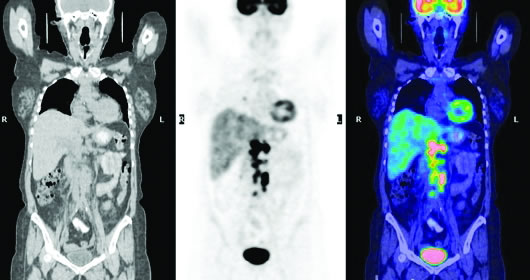

CT(左)、PET(中)及PET/CT(右)示NHL

正电子发射断层扫描 正电子发射断层扫描(PET)或PET/CT已经逐步应用于包括淋巴瘤在内的多种恶性肿瘤的诊断和疗效评价。与2007版相同,2008版《指南》仍然提供了两种淋巴瘤的疗效判定标准,一种是国际工作组1999年提出的淋巴瘤疗效评价标准(IWC),该标准以CT扫描为基础,包括完全缓解(CR)、未确定的完全缓解(CRu)、部分缓解(PR)、稳定(SD) 和进展(PD),另一种是新增加了PET扫描结果的疗效评价判定标准,该标准取消了CRu。但PET的应用范围主要局限在淋巴结或肿块病灶的判断上,对于肝脾和骨髓受侵的判断仍以查体、CT扫描或活检为标准。